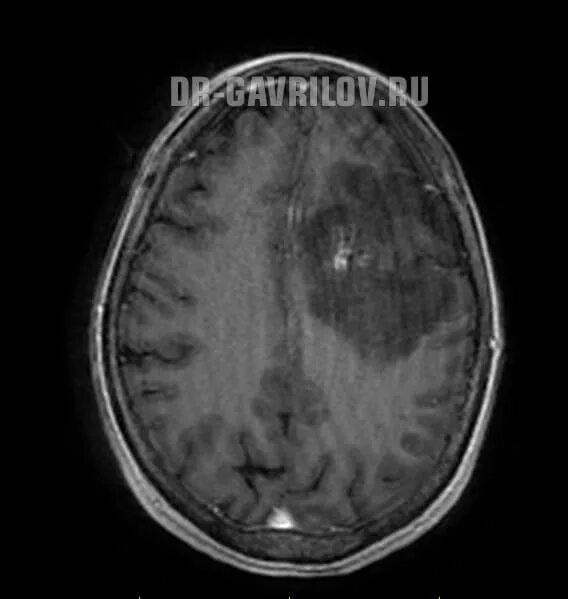

Астроцитома головного мозга прогноз после операции